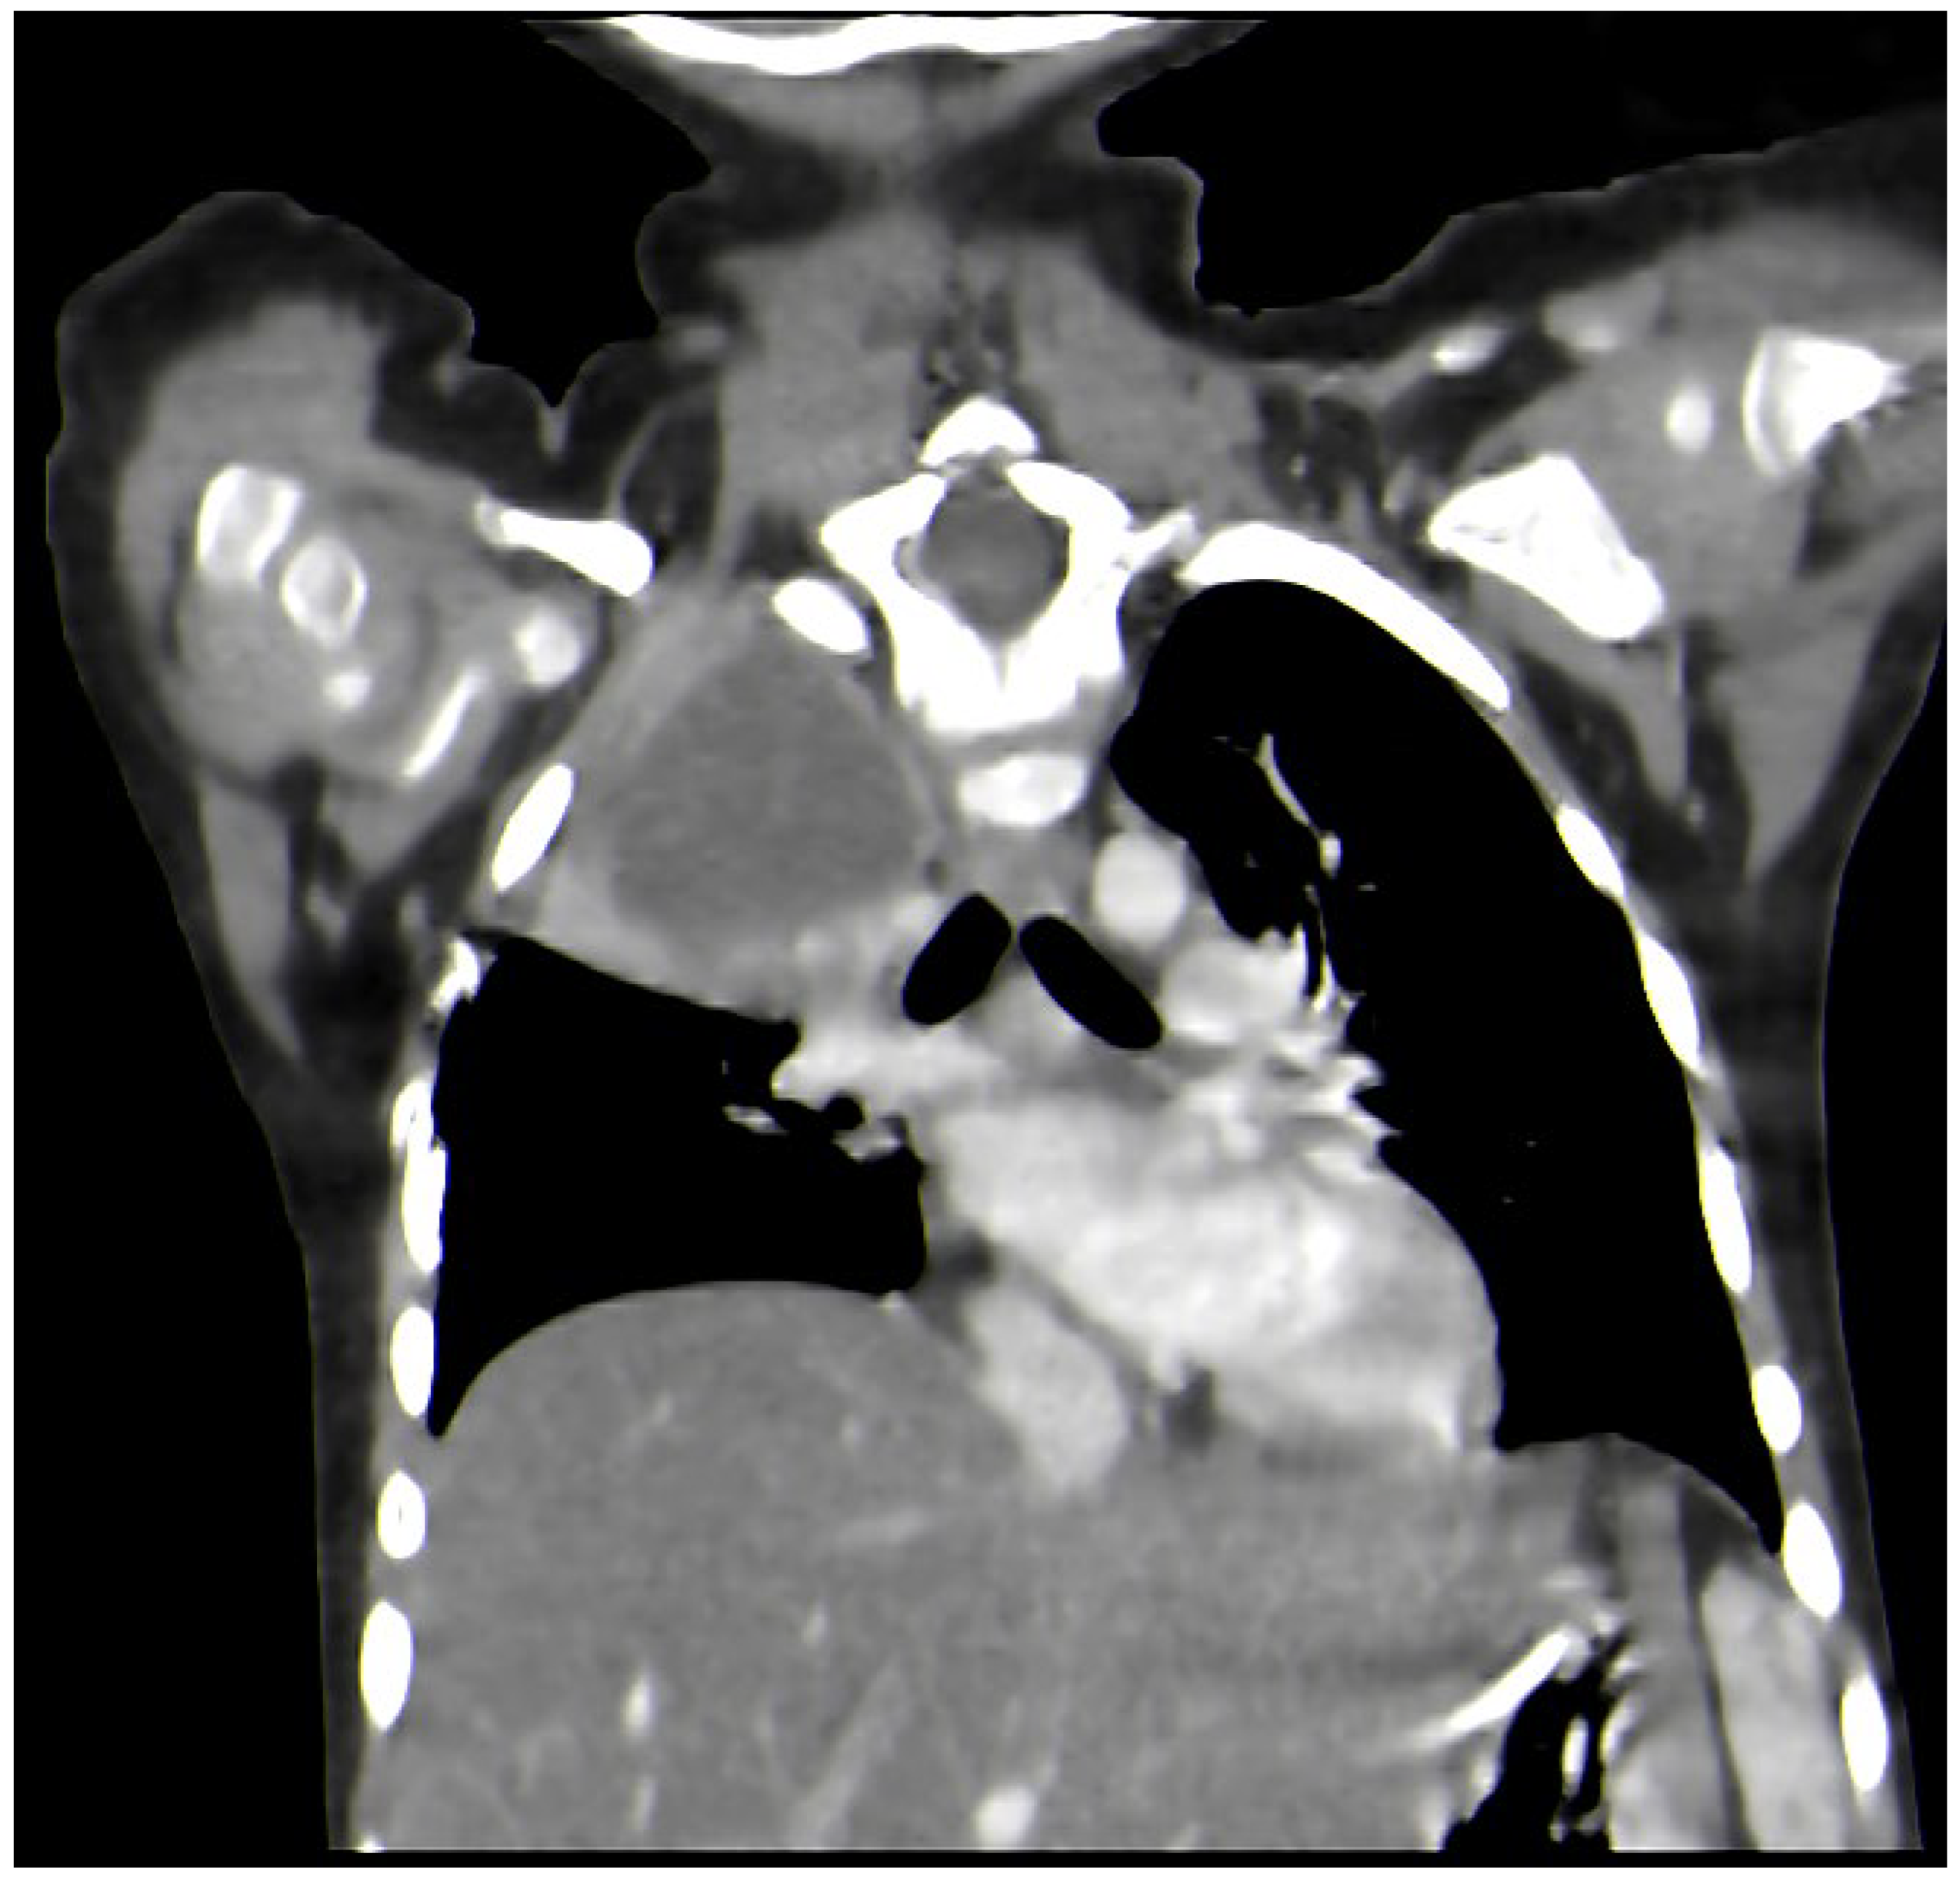

A Rare Case of Rhizomucor pusillus Infection in a 3-Year-Old Child with Acute Lymphoblastic Leukemia, Presenting with Lung and Brain Abscesses—Case Report

2. Case Report

Pahnev, Y.; Avramova, B.; Gabrovska, N.; Dontcheva, Y.; Tacheva, G.; Minkin, K.; Kreipe, H.; Yurukova, N.; Penkov, M.; Kartulev, N.; et al. A Rare Case of Rhizomucor pusillus Infection in a 3-Year-Old Child with Acute Lymphoblastic Leukemia, Presenting with Lung and Brain Abscesses—Case Report. Infect. Dis. Rep. 2026, 18, 2. https://doi.org/10.3390/idr18010002